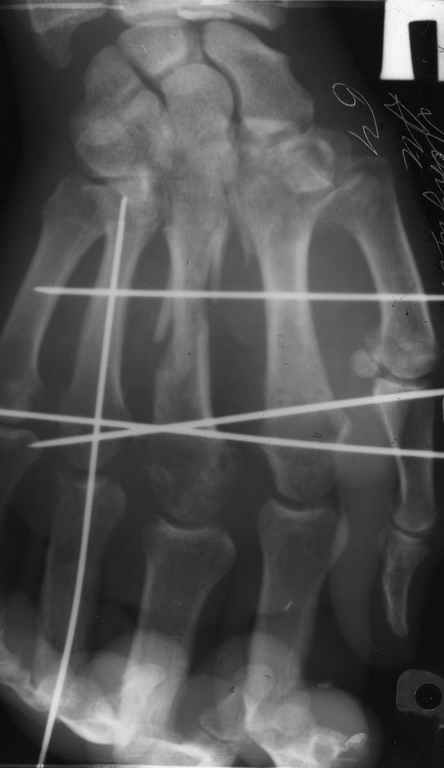

Диагноз: Стойкая Смешанная дермотеногенная контрактура 3,4 пальца правой кисти.